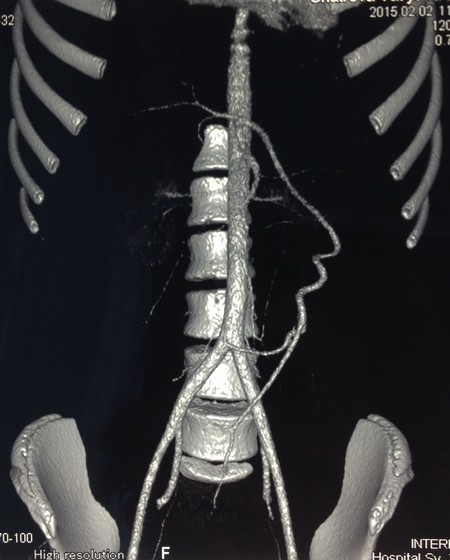

Девочка Ш. 13 лет госпитализирована в стационар для обследования по поводу увеличения селезенки, выявленного при УЗИ по месту жительства. На момент осмотра жалоб нет. Больная ведет активный образ жизни (занимается акробатическими танцами). В ходе УЗИ обнаружена увеличенная до 183x70 мм селезенка, расположенная в нижних отделах брюшной полости. Нижний полюс селезенки доходит до дна матки и мочевого пузыря, селезенка ротирована воротами к позвоночнику. Определяется массивный конгломерат извитых до 15мм в диаметре сосудов селезенки, при этом прослеживается ”whirlpool-sing”, сформированный извитыми сосудами с кровотоком преимущественно венозного характера. Выполнена спиральная компьютерная томография с болюсным введением контрастного вещества: cелезенка увеличена в размерах (42 х 23 х 12мм), расположена сразу за передней брюшной стенкой от уровня тела первого поясничного позвонка до уровня тела матки (4 крестцовый позвонок), где дислоцирует матку кзади. Контуры селезенки четкие, внутренняя структура однородная. Селезеночная артерия начинается в типичном месте от чревного ствола, значительно удлинена, ширина ее на всем протяжении от 4 до 5мм, направляется вниз и влево, имеет извитой, спиралевидный ход (Рис. 4)

Рис 4. Компьютерная томография. Селезеночная артерия значительно удлинена. Направляется вниз и влево, имеет извитой ход.

У больных с блуждающей селезенкой при пальпации живота может выявляться объёмное, легко смещаемое в область левого подреберья образование брюшной полости. Важное значение имеет УЗИ с определением кровотока в сосудах селезенки [1,2,6]. Спиральная компьютерная томография с контрастированием, а также МРТ позволяют визуализировать извитые сосуды ворот селезенки [5]. В обоих наших наблюдениях заподозрить перекрут блуждающей селезенки удалось при УЗИ. Наиболее характерным симптомом при спиральной компьютерной томографии, наряду с аномальным положением органа, был контрастируемый спиралевидный ход селезеночных артерии и вены.